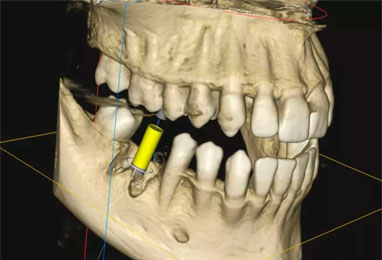

CBCT

CBCT (Cone Beam Computed Tomography) is an advanced 3D dental imaging technology that provides highly detailed and accurate images of the teeth, jawbones, nerves, and sinuses.

It helps dentists and specialists diagnose dental conditions with greater precision and plan treatments such as dental implants, root canal procedures, wisdom tooth removal, and jaw joint evaluations more effectively. CBCT scans are quick, painless, and use a lower radiation dose compared to traditional CT scans, making them a safe and reliable tool for modern dental diagnosis and treatment planning.